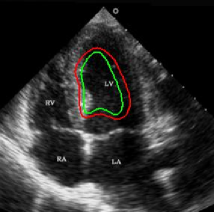

Refer to captionRefer to caption(a)(b)Refer to captionRefer to caption(c)(d)Refer to captionRefer to caption𝑎𝑏Refer to captionRefer to caption𝑐𝑑\begin{array}[]{cc}\includegraphics[width=112.0187pt,height=114.33119pt]{Ultra_init-1.pdf}&\includegraphics[width=112.0187pt,height=114.33119pt]{Ultra_Res-1.pdf}\\ (a)&(b)\\ \includegraphics[width=112.0187pt]{Ultra_init-2.pdf}&\includegraphics[width=112.0187pt]{Ultra_Res-2.pdf}\\ (c)&(d)\end{array}

Figure 13: Segmentation of endocardium in B-mode ultrasound images. (a) and (c) show the initializations provided, (b) and (d) show the converged contours. Image source: (a) was taken from [38] and (c) was taken from [39] .

In Figure 13, we show the results for segmentation of endocardium in B-mode ultrasound images, an imaging modality where shape prior information is popularly[40, 41] used to counter the problem of broken/diffuse boundaries between the region of interest and its background. In Figure 14, we show an example where the template based formulation is able to overcome partial loss of signal due to occlusion and still segment the object reliably. We observe that, by incorporating prior knowledge of the shape, we can segment images with partial loss of structure and broken boundaries.

We next develop templates for objects with hole(s) in their structure. These templates are called ring templates. Figures 15 and 16 show examples of ring templates. The area enclosed between the red contours act as region 1subscript1\Re_{1} and the area between the green contours is region 0subscript0\Re_{0}. Figure 17 shows the construction of the ring contours. The two seemingly unconnected contours are actually one connected contour. Hence, partial derivative calculations in equation (26) are still valid.

In Figure 15, the ring template has been used for segmenting the left ventricular (LV) wall of heart in cardiac MR images. Another example is shown in Figure 16. The template used in both examples has a greater thickness in the inner ring-shaped annular region than the outer annular region. This was done to facilitate obtaining the desired object’s structural information by means of the contrast (for example, between the endocardium and the LV wall) that a good initialization can offer. Hence, while designing a template, we can incorporate prior knowledge of the object and its surroundings.